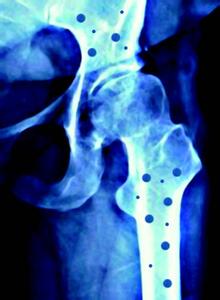

磷在人体内的含量仅次于钙,约占体重的1%。全自动星空体育成年人体内磷的含量是500一600克,其中90%存在于骨骼中,10%存在于细胞内。在软组织中的磷主要以有机磷、磷脂和核酸的形式存在。在骨组织中所含的磷主要以无机磷的形式存在,即与钙构成骨盐成分。血浆中磷分为有机磷和无机磷两类,与蛋白结合的磷称为有机磷,占大部分。血液中的磷完全以无机磷酸盐的形式存在,在骨内与钙结合成不稳定的磷酸钙,并与骨不断地进行交换。

磷存在于所有动、植物中,磷的来源主要是饮食,牛奶及乳制品、肉蛋类、蔬菜、坚果、豆制品中均含有丰富的磷。只要注意饮食营养丰富,一般情况下,并不存在饮食磷的缺乏问题。食物中的磷,不论是以有机磷的形式还是无机磷的形式存在,均能在胃肠道吸收。摄入量的范围一般在500—2000毫克/天。大多数食物的磷必须在肠道中变成无机磷才能被吸收,有机磷如磷脂可以直接被肠道吸收。磷主要的吸收部位在小肠,按小肠各部的吸收能力,依次是空肠、十二指肠和回肠。肠磷吸收的方式是由两条途径完成的:一条是由细胞途径,即细胞调节磷的主要转运过程;另一条是由细胞旁道,是磷的被动弥散的途径。正常成人每日磷的需要量为880毫克,孕妇、儿童要稍多一点,摄入的磷有60%被再吸收。肠磷吸收受很多激素的影响,但主要受维生素D的控制,如果钙的摄人过多,会使磷酸盐变为不可溶,使磷的吸收减少。

肾脏是调节磷代谢的主要器官。血磷可以自由通过肾小球滤过膜,因此原尿中磷的浓度与血磷相同。在近端小管、原尿中85%的磷被再吸收,远端小管及部分肾单位可重吸收原尿10%的磷。所以肾小球滤过和近端小管对磷的重吸收是影响磷代谢的重要因素。在生理情况下,机体主要是通过近端小管对磷的重吸收来调节磷代谢的。

全自动星空体育分析甲状腺激素是一种增加尿磷的激素,不但可以减少肾小管对磷的重吸收,同时还增加骨磷的动员。由于两种相反作用使甲状旁腺素对磷代的调节所起的作用受到限制,维生素D在肾磷调节方面,有对肾小管重吸收减少的结果。最近提出了降磷素,它是体内一种激素,与磷代谢有关。它可以抑制近端小管上皮细胞刷状缘上NA-P共转运体对磷的重吸收,使钠、磷减少,从而导致肾小管对磷的重吸收减少以致血磷降低。正常人血磷的浓度为0.8—1.5毫摩尔/升。